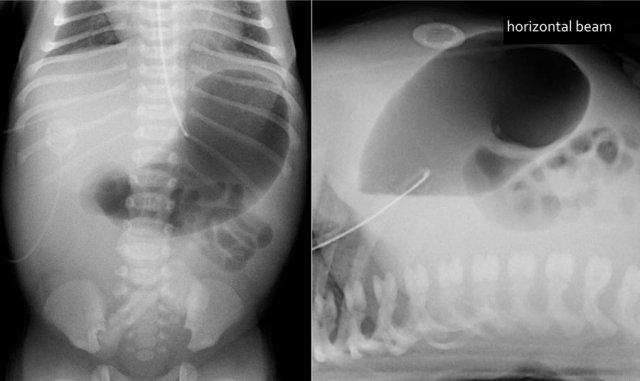

Các hình ảnh cho thấy một trường hợp điển hình của viêm ruột hoại tử với khí trong thành ruột.

Trên hình chụp tia ngang, không có dấu hiệu khí tự do trong ổ bụng.

Đây là hình ảnh của một trẻ sơ sinh phát triển viêm ruột hoại tử.

Ở giai đoạn sớm này, X-quang chỉ cho thấy hình ảnh giãn ruột không đặc hiệu.

Ở giai đoạn này, không thể xác lập chẩn đoán.